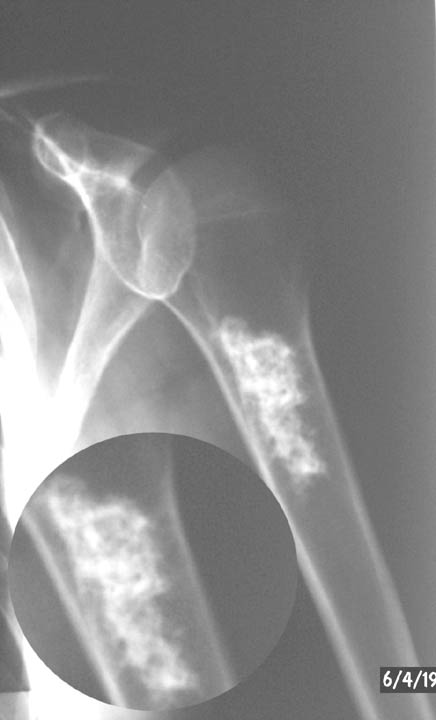

Рентгеновские снимки саркомы плечевого сустава